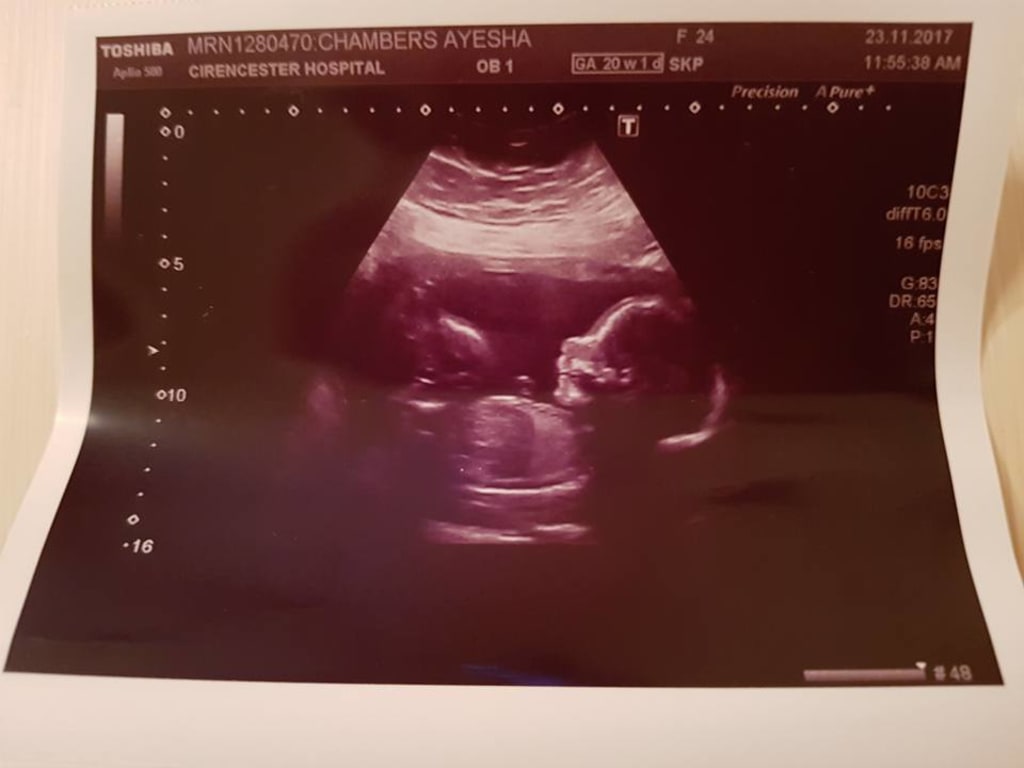

To anyone looking at the image attached to this story, they can simply see an ultrasound. When I look at this image, I see so much more. This ultrasound is of my current pregnancy with my little boy Freddie-Ray, due in April 2018. To say me and my partner are ecstatic is a huge understatement, in more ways than one. Let me take you back to June 2016.

I'm so sorry! I went through the same thing, my daughter Raelyn had anencephaly she lived 23 days 1/13/2020-2/5/2020. I'm very confused from your ultrasound picture though because I see skull and brain my daughter didn't have any of that her ultrasound pictures had nothing above her eyes and she had a lot more then what some anen babies have if you go to my stories and take a look you can see what she looked like. I honestly believe they misdiagnosed your child because the baby would of looked a lot different on the ultrasound. I hope I'm not coming off as rude or insensitive or anything like that I am just genuinely concerned that they might have made a mistake